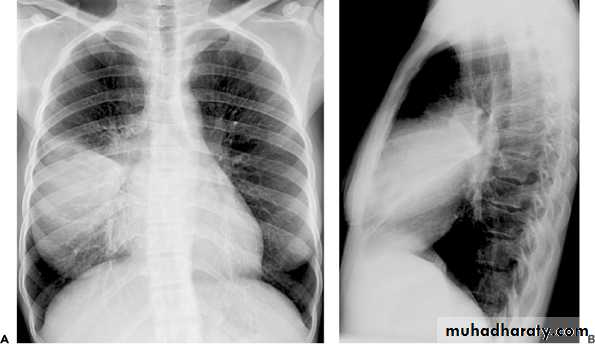

Lobar pneumonia due to Streptococcus pneumoniae.

Extensive right middle lobe consolidation.• .